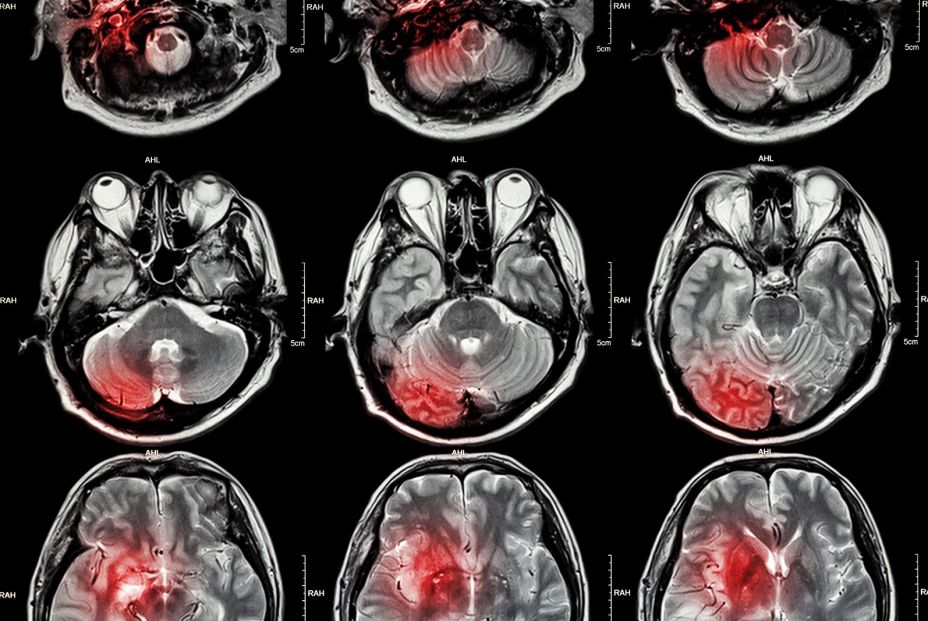

Alude, además, a que puede ocurrir a cualquier edad. De hecho, en los últimos años se ha incrementado su incidencia en un 25% en edades comprendidas entre 20 y 64 años, si bien es más frecuente a partir de los 65 años. Y los estudios prevén un aumento significativo de su incidencia. Existen dos tipos principales de un evento cerebrovascular: el isquémico ,que se presentan debido al bloqueo en una arteria, y el hemorrágico a consecuencia de una ruptura o fuga en un vaso sanguíneo

El accidente cerebrovascular isquémico es causado por un bloqueo del flujo sanguíneo al cerebro y es el tipo más común de accidente cerebrovascular. La tenecteplasa, un fármaco trombolítico más reciente, está aprobado para el tratamiento del ictus isquémico en Europa, pero no en los EEUU. Está autorizado en este últi páis para el tratamiento de coágulos que bloquean las arterias coronarias y se utiliza fuera de indicación para el ictus isquémico en algunos centros especializados en ictus.